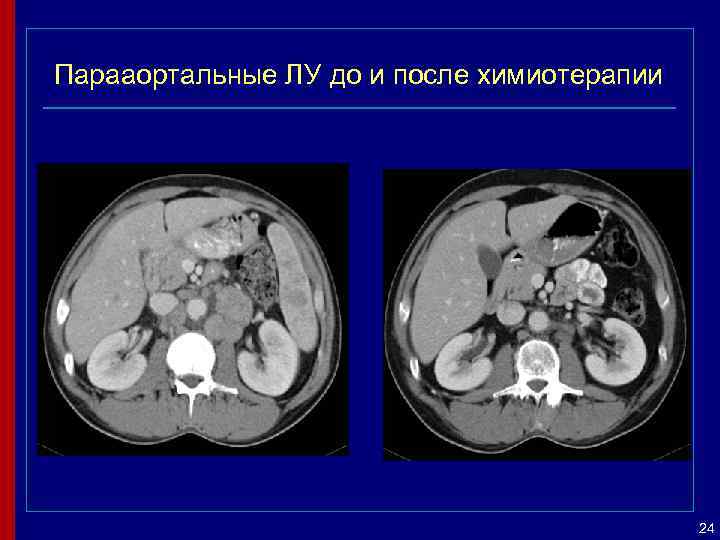

Парааортальные ЛУ до и после химиотерапии 24